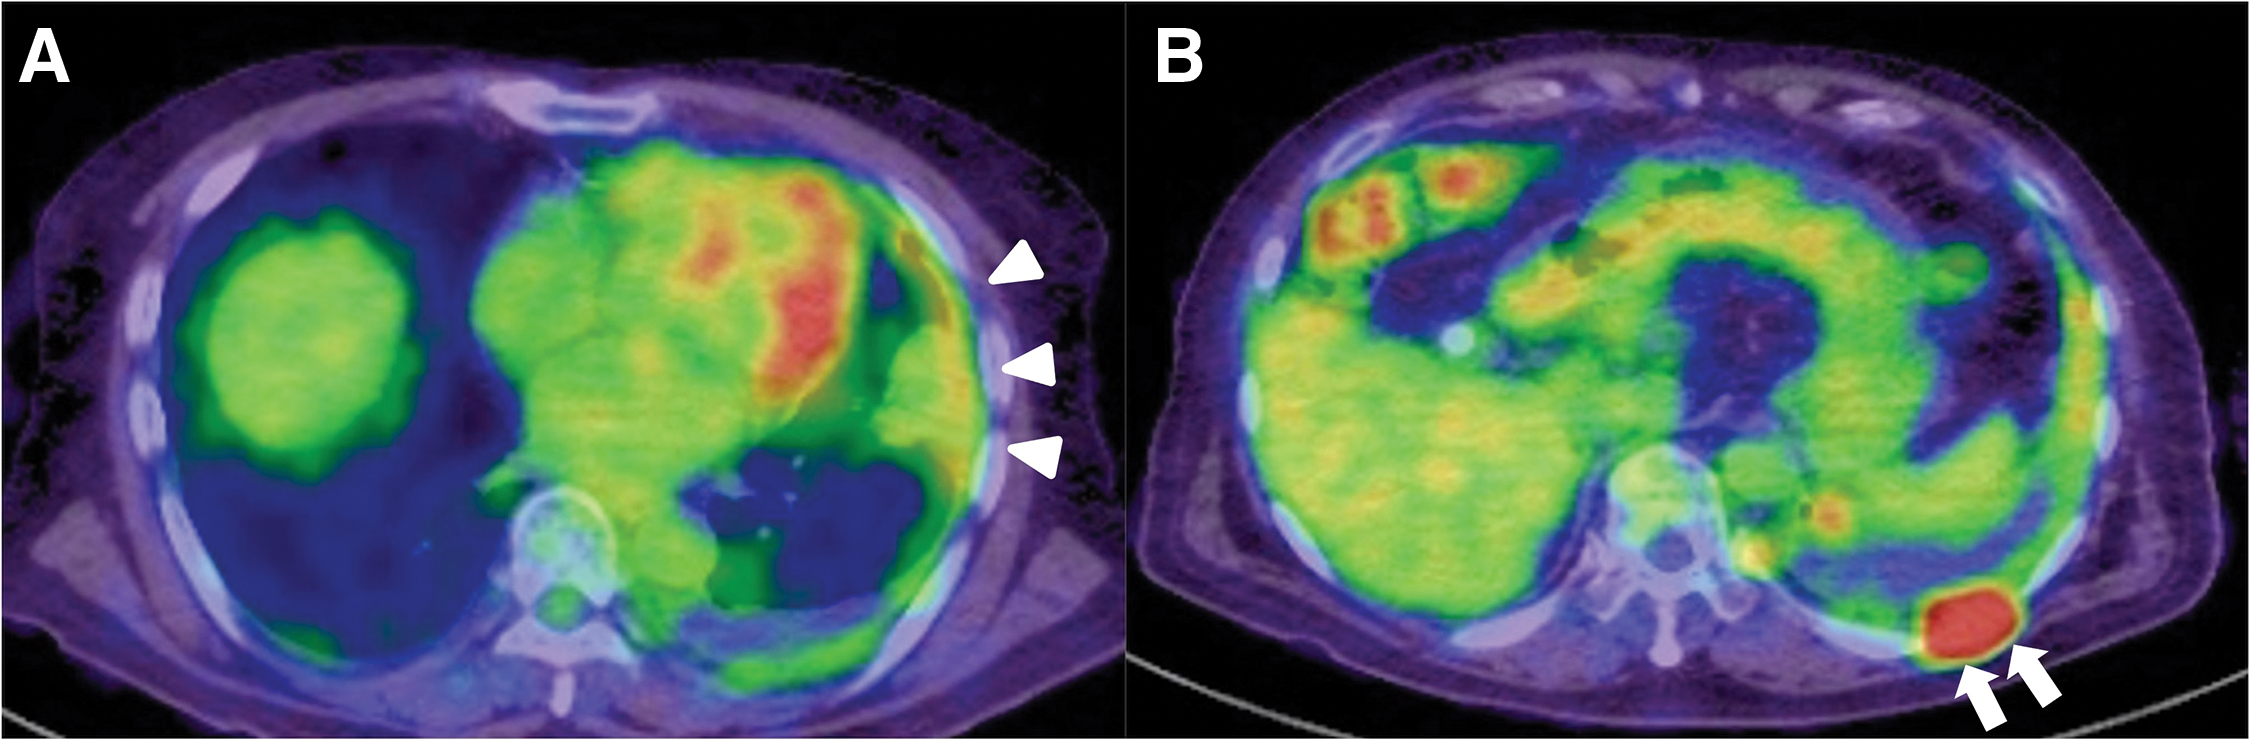

An 81-year-old man with a history of asbestos exposure presented to our hospital with sudden onset of dyspnea. Based on positron emission tomography/computed tomography (PET/CT) reports showing pleural accumulation (Fig. 1), a surgical pleural biopsy was performed 10 months prior to surgery. The patient was diagnosed with cancer at an unknown primary site, which was suspected to be a lung adenocarcinoma or malignant mesothelioma. He received seven courses of immune checkpoint inhibitor treatment, similar to the treatment for non-small cell lung cancer, until 6 months prior to surgery. He also had a history of hypertension, diabetes, epilepsy, unruptured brain aneurysms, and was undergoing treatment for prostate cancer. On examination, the patient was orthopedic, tachypneic, and hypoxic despite oxygen administration. Blood samples showed an elevated inflammatory response, anemia (hemoglobin: 9.8 g/dL and hematocrit: 31.9%), mild renal dysfunction (blood urea nitrogen: 31.1 mg/dL, creatinine: 0.99 mg/dL, and estimated glomerular filtration rate: 55.6 mL/min/1.73 m2), markedly elevated brain natriuretic peptide (BNP) (2480 pg/mL) and markers suggestive of disseminated intravascular coagulation (platelets: 3.8 × 104/μL, prothrombin time: 16.5 s, fibrin/fibrinogen degradation products: 64 μg/mL, and D-dimer: 16.4 μg/mL). Transthoracic echocardiography revealed a fragile and mobile tumor occupying the right atrium (Fig. 2A), and the patient was admitted for surgical tumorectomy. Preoperative contrast-enhanced CT could not be performed because of a history of allergy to contrast media. The operation was performed urgently using a cardiopulmonary bypass via a full sternotomy. The pericardium is grossly intact and does not adhere to the heart. A 3 × 5 cm tumor was tightly attached to the right atrium and was large enough to easily fit into the tricuspid valve. Therefore, the entire margin of the tumor stem attachment was resected (Fig. 2B). The patient was transferred to the intensive care unit (ICU) for ventilatory management, was extubated on postoperative day (POD) 4, and discharged from the ICU on POD 17, followed by discharge on POD 54. Additional anticancer therapy was considered but was not suitable due to the patient’s physical condition being significantly reduced. Consequently, the patient died of pneumonia 2 months after surgery. Autopsies were not performed as the request of the family.